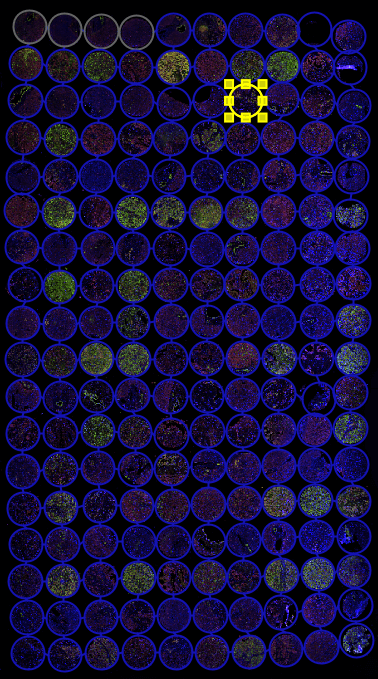

TMA分割模块,支持多样本来源组织芯片图像研究

TMA区域自动分割无需手动拆分cores

TMA分割